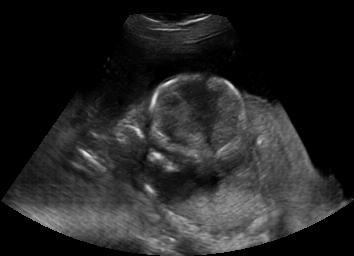

Real in-vivo images. 22 ultrasound sequences were collected using a GE Voluson E8 machine during standard fetal screening exams of 8 patients. Each sequence is several seconds long. We extracted all 4427 frames and resize them to , see Fig. 2 for some examples. The resulting image set was randomly split into training-validation-test sets by a 80-10-10% ratio.